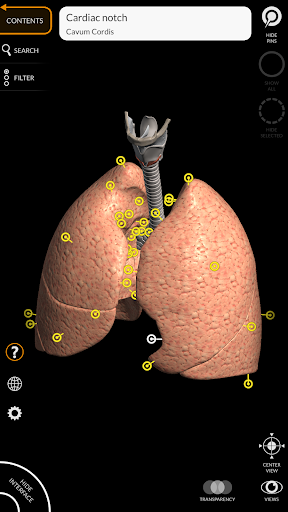

"Anatomy 3D Atlas" vous permet d'étudier l'anatomie humaine de manière simple et interactive.

Grâce à une interface simple et intuitive, il est possible d'observer chaque structure anatomique sous n'importe quel angle.

Les modèles anatomiques 3D sont particulièrement détaillés et avec des textures jusqu'à une résolution de 4k.

La subdivision par régions et les vues prédéfinies facilitent l'observation et l'étude de parties individuelles ou de groupes de systèmes et les relations entre différents organes.

• Système respiratoire

• Faites pivoter et zoomez chaque modèle dans l'espace 3D

• Option pour masquer ou isoler un ou plusieurs modèles sélectionnés

• Filtrez pour masquer ou afficher chaque système

• Fonction de recherche pour trouver facilement chaque partie anatomique

• Fonction de transparence